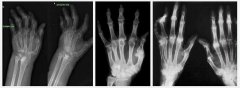

类风湿关节炎(RA)是一种病因未亮的慢性、以炎性滑膜炎为主的系统性疾病,其特征是手、足小枢纽关头的多关节、对称性、侵袭性关节炎症,经常陪同枢纽关头外器官受累及血清类风湿